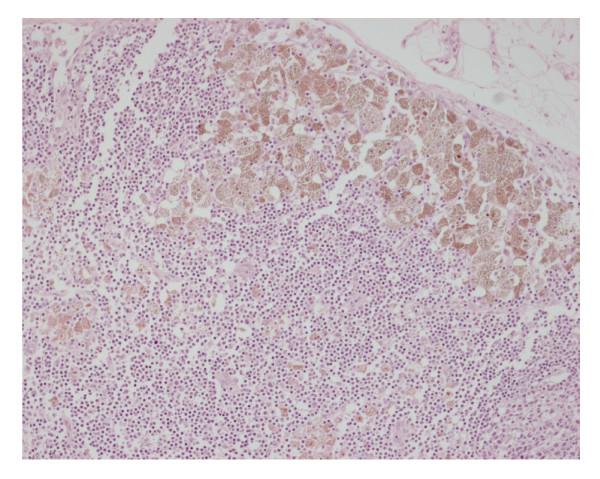

Melanosis Coli is described as black or brown discolouration of the mucosa of the colon. Its a benign condition, which arises from anthraquinone laxative abuse and has no symptoms of its own. The main importance of diagnosing Melanosis Coli correctly lies in the fact that if its extensive, there may be difficulty in differentiating it from ischemic colitis.

We present a case of extensive Melanosis Coli involving the whole of large bowel that appeared gangrenous. A sub total colectomy was performed on presumed diagnosis of ischemic bowel.